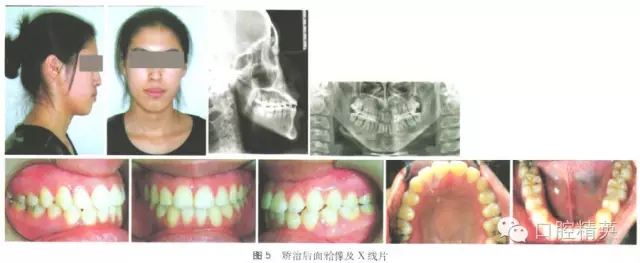

矯治后面型改善良好,直面型。雙側(cè)磨牙完全近中關(guān)系,前牙覆牙合覆蓋正常,上下牙排列整齊,上下中線(xiàn)居中、對(duì)齊,上下牙齒基本為尖窩鎖結(jié)關(guān)系。矯治結(jié)束后囑患者拔除四顆智齒。曲面斷層片顯示:牙根平行排列,未見(jiàn)明顯牙根吸收,治療前后頭影測(cè)量值見(jiàn)表1,治療前后頭影測(cè)量重疊圖見(jiàn)圖1,治療前中后面牙合像、X線(xiàn)片見(jiàn)圖2~5。